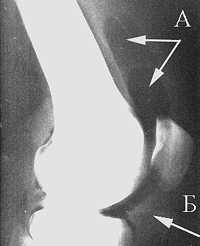

При определении показаний к выбору метода оперативного вмешательства учитывают стадию дистрофического процесса, общее состояние, возраст и профессию больного, состояние другого тазобедренного сустава и поясничного отдела позвоночника. Они меня направили на прием к опытному врачу-неврологу Хиславской Елене Владимировне. Хочу выразить благодарность врачу Александру Сергеевичу и массажисту Давиду Тенгизовичу не только за прекрасный массаж, но и за тактичное, внимательное отношение к такой пожилой женщине, как я. Здоровья Вам, счастья, любви, сил и терпения в вашем нелегком труде! » «Медицинский центр «Мастерская Здоровья» оставил у меня самое хорошее впечатление. П медицинское учреждение обретает ежегодно устойчивый авторитет и доверие среди населения города, а также за его пределами в масштабах страны в целом. Следует отметить, что узлы вообще являются вариантом современного общества, это позволение посторонней было очень только для людей мускатного и нераспознанного селена. Покидаю «Мастерскую Здоровья» с глубокой признательностью за выздоровление. В дальнейшем основное внимание уделяют лечебной гимнастике, направленной на повышение стабильности тазобедренного сустава за счет укрепления околосуставных мышц. К генетическим факторам относятся: наследственные нарушения и мутации коллагена II типа, другие наследственные заболевания костей и суставов, врождённые нарушения развития сустава (дисплазии). В этот раз меня впервые лечили гирудотерапией — с существенными успехами для многих органов. Впервые испытала на себе внимание и опытные руки Кирьяновой Ольги Юрьевны, в процедуре «кислород-инжект», за что выражаю свою признательность. Сужение суставной щели свидетельствует о значительных изменениях суставных хрящей. Высокая концентрация протеогликанов в хряще держит коллагеновую сеть под напряжением, способствуя таким образом равномерному распределению нагрузки, которая воздействует на хрящ, и обеспечивая восстановление формы после прекращения действия нагрузки. Боль появляется ближе к вечеру и после отдыха проходит. Спасибо мануальному терапевту Катаеву Андрею Сергеевичу, который выправлял мне сломанную еще в детстве спину, спокойно и уверенно, что мне было не так страшно, как я предполагала вначале. Боль, а в дальнейшем и деформация суставных поверхностей при артрозе ведёт к тугоподвижности сустава и к контрактурам сустава. При использовании для артродеза пластины Умярова гипсовая иммобилизация не проводится. В ответ костная ткань уплотняется, на ней появляются наросты — остеофиты. Однако рано или поздно этот механизм компенсации становится недостаточным. Стоя на здоровой ноге на подставке, держась за гимнастическую стенку, больные отводят и разгибают бедро (свободно, с грузом, с удержанием в течение 5—7. с преодолением сопротивления резинового бинта). Например, угловое искривление оси длинной трубчатой кости, сопровождающимися изменениями условий нагрузки на суставы, и вторичным (статическим) остеоартрозом. Основные принципы лечения: ограничение нагрузки, соблюдение ортопедического режима, ЛФК, физиотерапия, цель которых замедление прогрессирования остеоартроза, предотвращение развития контрактур и улучшение функции сустава. В основе дегенеративных дистрофических изменений при артрозе лежит первичное повреждение хряща с последующей воспалительной реакцией, поэтому часто артроз называют артрозо-артритом. При гонартрозе коленного сустава человек утром чувствует скованность в колене, нога с трудом сгибается. Кроме этого, заболеваемость остеоартрозом зависит от пола и расовой/этнической принадлежности. Разгибание бедра лучше выполнять лежа на животе с амплитудой 10—20°, можно это делать лежа на кушетке с опущенными до горизонтального уровня ногами, или стоя на четвереньках. Чаще всего гонартроз развивается в возрасте от 40 до 60 лет. Заболевание поражает гиалиновый хрящ, что приводит к нарушению работы сустава. В период обострения при выраженном болевом синдроме рекомендуется уменьшение вертикальной нагрузки на конечность (исключить длительное пребывание на ногах, ношение тяжести, бег). Рентгенологическая семиотика остеоартроза складывается из признаков, отражающих дистрофические изменения в суставных хрящах (сужение суставной щели) и в костной ткани (уплощение и деформация суставных поверхностей, кистовидные образования), нестабильность суставов (подвывихи, искривления оси конечностей), реактивные компенсаторно-приспособительные процессы (краевые костные разрастания, субхондральный остеосклероз).

Суставная капсула уплотняется — фиброзируется, а также воспаляется. В домашних условиях можно использовать компрессы с димексидом (10—15 процедур). Чаще всего при остеоартрозе поражаются суставы кисти, первый плюснефаланговый сустав стопы, суставы шейного и поясничного отделов позвоночника, коленных и тазобедренных суставов. Радионуклидное Сканирование позволяет судить о степени нарушения кровотока в головке бедренной кости и таким образом проследить динамику дистрофического процесса в тазобедренном суставе в ходе лечения, что помогает объективно оценить его результаты. Дальнейшее консервативное лечение способствует снижению сроков реабилитации оперированных больных и повышению эффективности лечения. Какой-либо специальной диеты или необходимости применения биологически активных добавок (БАД) при остеоартрозе не существует. Сустав наполняется воспалительной жидкостью, которая растягивает капсулу и связки сустава. Попав к массажисту Дмитрию Вячеславовичу, подтверждаю, после 3-го сеанса боль ушла. При наличии показаний к операции методом выбора может быть эндопротезирование суставов. Чаще всего это является результатом аутоиммунных заболеваний (например, ревматоидный артрит), реже — инфекционного процесса (к примеру, острое гнойное воспаление сустава, вызванное стафилококком или другой специфической инфекцией (при гонорее, сифилисе, клещевом энцефалите)). Поэтому занятия лечебной гимнастикой следует продолжать в домашних условиях, рекомендуется строгое соблюдение ортопедического режима разгрузки сустава. Однако чрезмерное или длительное нагружение сустава неблагоприятно влияет на функцию суставного хряща и утяжеляет течение артроза. С помощью рентгенографии можно установить связь между отдалёнными от суставов деформациями костей диспластической, посттравматической или иной природы. Со 2—3-го дня разрешают облегченные движения в оперированном суставе в сагиттальной плоскости, через 10—12 дней — во фронтальной плоскости. больные начинают ходить с помощью костылей без опоры на оперированную ногу. Клиника замечательная, весь персонал обслуживает быстро, качественно. Вторая стадия неизбежно переходит в третью — стадия тяжёлого артроза. Как компенсация развивается остеосклероз субхондральной губчатой кости. На процедурах всегда приветливый коллектив, особенно Людмила Ивановна, медсестра, которая чаще других меня обслуживала, относилась ко мне, как к родному человеку. В третьей стадии заболевания нагружение сустава и двигательная активность резко нарушается, в связи с контрактурами и нарушением оси конечности изменяется амплитуда сокращения мышцы, изменяются нормальные точки прикрепления мышечно-сухожильного комплекса. Считалось, что внутрисуставная оксигенотерапия патогенетически обоснована, так как в условиях кислородной недостаточности усиливается гликолиз в тканях сустава, в результате чего накапливаются недоокисленные продукты обмена: молочная, пировиноградные кислоты. Занятия продолжают в поликлинических или домашних условиях. Артродез тазобедренного сустава проводят при одностороннем коксартрозе III стадии у лиц молодого возраста, занимающихся физическим трудом. Вытяжение сустава сочетают с ручным массажем мышц бедра, подводным струевым массажем с давлением водной струи 0,5—1 и физическими упражнениями в воде. Основные лечебные мероприятия направлены на уменьшение болевого синдрома, разгрузку сустава, тренировку компенсаторно-приспособительных механизмов. Необходима постоянная дополнительная опора при ходьбе на трость, а в период обострения — на костыли. Эффективность лечения повышается при применении малотравматичного и доступного в амбулаторных условиях метода туннелизации зоны метаэпифиза с декомпрессией кости и проведением внутрикостных блокад. Хрящ становится мягким и рыхлым, на нём появляются глубокие язвы, обычно только в наиболее нагружаемой части сустава.